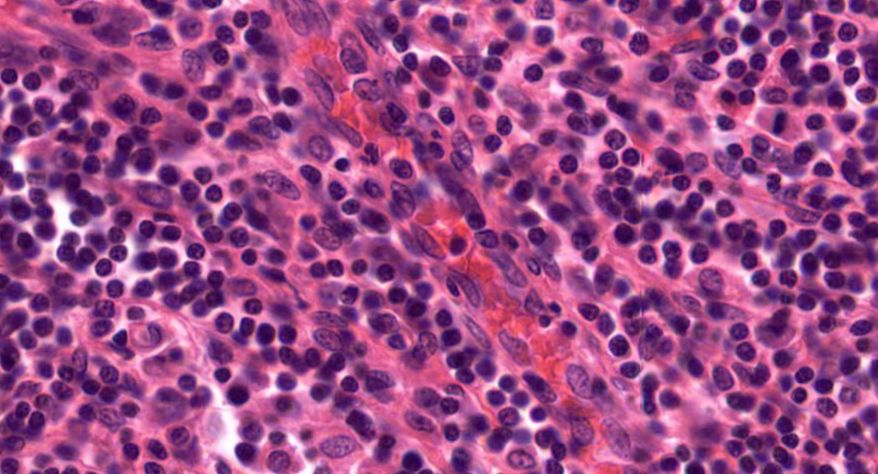

低倍镜:胸腺表面包有薄层结缔组织构成的被膜,结缔组织深入实质,将胸腺分成许多不完整的小叶。每个小叶分为周围的皮质和中央的髓质两部分。皮质中胸腺细胞排列密集,故染色深;髓质中胸腺细胞较少,胸腺上皮细胞多,故染色浅,其中可见染成红色的圆形小体-胸腺小体。高倍镜:胸腺小体大小不等,由几层至十几层扁平的胸腺上皮细胞呈同心圆状排列而成,其外周的细胞较幼稚,细胞核明显;小体中央部分的上皮细胞已退化,细胞核消失,胞质呈均质状,染成红色。